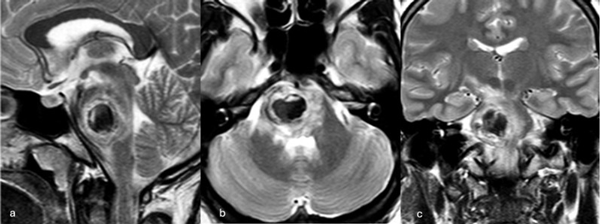

Una mujer de 53 años, con antecedentes de dos sangrados previos, consultó por un cuadro de perfil agudo caracterizado por tetraparesia asociada a compromiso de pares craneales bajos, que requirió instalación de una traqueostomía. La RM de encéfalo evidenció una malformación cavernomatosa en relación al bulbo izquierdo (Figura 9). Un mes después del último sangrado, la paciente fue sometida a una exéresis de la lesión mediante un abordaje suboccipital de línea media, vía intertonsilar (Figura 10), logrando una exéresis completa (Figura 11). Luego de la cirugía la paciente evolucionó con mejoría parcial de sus síntomas de ingreso, sin agregar nuevos déficits neurológicos.

Figura 9. RM preoperatoria de encéfalo. Se evidencia una lesión única intraaxial bulbotrigonal izquierda, que contacta la mitad inferior del piso del cuarto ventrículo, hiperintensa en T1 y T2, con vacíos de flujo que impresionan provenir de una malformación del desarrollo venoso, lo que sugiere una malformación cavernomatosa. A) Imagen en corte sagital ponderada en T1 posterior a la administración de gadolinio. B y C) Imágenes en corte axial ponderadas en T1 y T2, respectivamente.